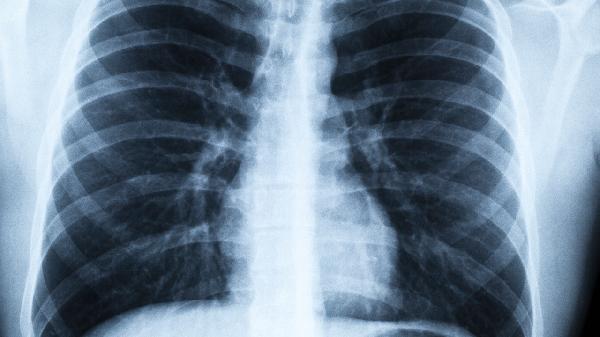

肺功能检测就像给呼吸系统做“体检报告”,但很多人拿到结果后都会困惑:这份报告的有效期到底是多久?其实答案并不像保质期那样简单明确,关键要看你的年龄、职业和生活状态。

肺功能检测没有绝对的“有效期”,就像汽车需要定期保养一样,我们的呼吸系统也需要动态监测。特别是出现不明原因的体力下降、运动耐力降低时,别简单归咎于“年纪大了”,很可能是肺部发出的求.救信号。建议从40岁开始把肺功能检测纳入常规体检项目,毕竟能自由呼吸的日子,才是真正有质量的生活。